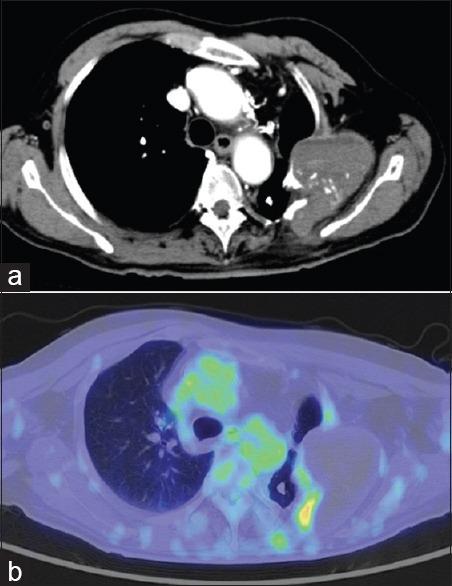

The brain metastasis of angiosarcoma is very rare, and little is known about its clinical features or therapeutic strategy. A 74-year-old male was hospitalized for disturbance of consciousness. Radiological examination revealed multiple cerebral hematomas. Gadolinium contrast-enhanced magnetic resonance imaging showed no significant enhancement at any of the lesions. To detect a suspected metastatic brain tumor or abscess, a full-body scan was performed but revealed only a poorly enhanced mass in the removal cavity caused by thoracoplasty in the left upper chest. After admission, a cascade of expansion of those hematomas occurred in the right frontal, left parietal, and right temporal lobes, and each lesion thus had to be sequentially removed by craniotomies. The pathological diagnosis of the right frontal lesion was an abscess with hematoma. However, a malignant vascular tumor was highly suspected because of many CD31(+)/Ki-67(+) cells in the left parietal lesion. A mass in the scar caused by thoracoplasty was suspected to be the primary lesion, and brain metastasis of angiosarcoma was finally diagnosed. Whole-brain irradiation and systemic paclitaxel administration were performed, and a complete response for the brain lesions was obtained for 22 months; the patient then died of an intratracheal hemorrhage. This case represents the first report of multiple brain metastases from pyothorax-associated angiosarcoma accompanied by sequentially and gradually expanding hematomas, as well as the first case with the control of metastatic brain lesions for over 1 year after the onset of neurological symptoms. Control of the lesions could be achieved by their total removal with complete hemostasis, as well as additional radio- and chemotherapy.

血管肉瘤脑转移非常罕见,其临床特征或治疗策略鲜为人知。一名74岁男性因意识障碍入院。影像学检查发现多处脑血肿。钆增强磁共振成像显示任何病变均无明显强化。为检测疑似转移性脑肿瘤或脓肿,进行了全身扫描,但仅发现左上胸部胸廓成形术切除腔内有一个强化不佳的肿块。入院后,右额叶、左顶叶和右颞叶的血肿相继扩大,因此每个病变都必须通过开颅手术依次切除。右额叶病变的病理诊断为血肿性脓肿。然而,左顶叶病变中存在许多CD31(+)/Ki-67(+)细胞,高度怀疑为恶性血管肿瘤。胸廓成形术瘢痕处的肿块被怀疑是原发灶,最终诊断为血管肉瘤脑转移。进行了全脑照射和全身紫杉醇给药,脑病变获得了22个月的完全缓解;患者随后死于气管内出血。本病例代表了第一例脓胸相关性血管肉瘤多发脑转移并伴有血肿依次逐渐扩大的报告,也是第一例神经症状出现后转移性脑病变得到控制超过1年的病例。通过彻底止血的完全切除以及额外的放疗和化疗可以实现病变的控制。